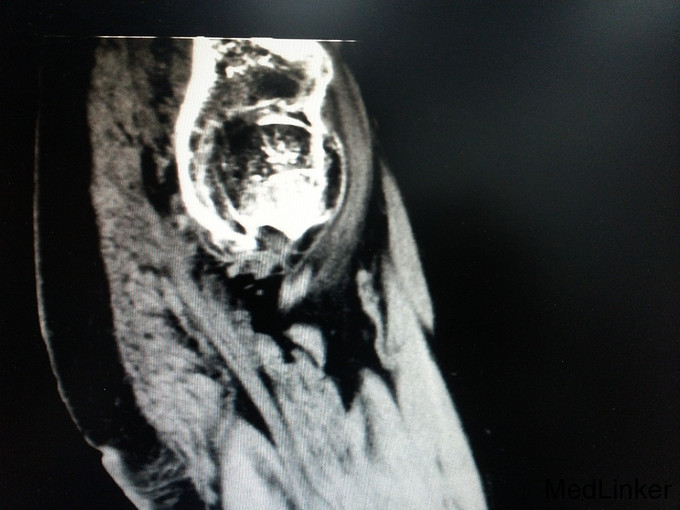

讨论: 经验:强直性脊柱炎累及双髋的患者行全髋关节置换术时,显露及找到髋臼是手术的重点和难点。 1.显露。由于髋关节强直,失去活动度,助手在不能旋转大腿,造成显露困难。我们的做法是先充分显露小粗隆,沿小粗隆上方约2cm处截骨(一般常规于小粗隆上方0.5-1cm处截骨),充分离断头颈部,此时助手可通过内旋患肢,充分显露。下一步再按常规行小粗隆上截骨。 2.清除瘢痕组织。此类患者由于长期髋部强直,活动受限,周围往往会形成瘢痕挛缩,多以内收肌紧张常见。故显露的过程需彻底清除周围瘢痕组织。术中安装假体后测试关节各方西活动,若内收肌紧张,需行内收肌松解。 3.找髋臼。由于强直性脊柱炎累及髋关节需行关节置换的患者,往往头与髋臼已经发生融合,术中很难判断髋臼。若贸然凿除所谓的股骨头,很可能会破坏髋臼壁。故找髋臼时性循序渐进,逐渐凿骨找到髋臼。CT片显示头与髋臼底之间仍有间隙存在,故可推断圆韧带仍存在,这也是这类患者的特点。故逐渐凿除股骨头时,到达圆韧带的层面时就找到了髋臼底。此时可开始磨钻磨锉髋臼。从小号开始依次增大号数。 4.骨质。强直性脊柱炎的患者因长期服用激素类药物,骨量丢失较正常人较多,故髋臼骨质疏松明显,所以磨搓髋臼时需反转,防止骨量过度丢失,磨穿髋臼。 不足:1.术中由于患者左髋强直,摆放手术体位受限,不能维持身体中立位,身体后仰,术中安放臼杯时未能把握合适的前倾角度。 2.假体的选择。由于术前未认真评估股骨髓腔的形态,导致术中按常规选择股骨假体柄后,出现假体柄打入困难。该患者股骨髓腔形态呈烟囱型,最好选择直柄,打入后可更贴合,方便骨长入。